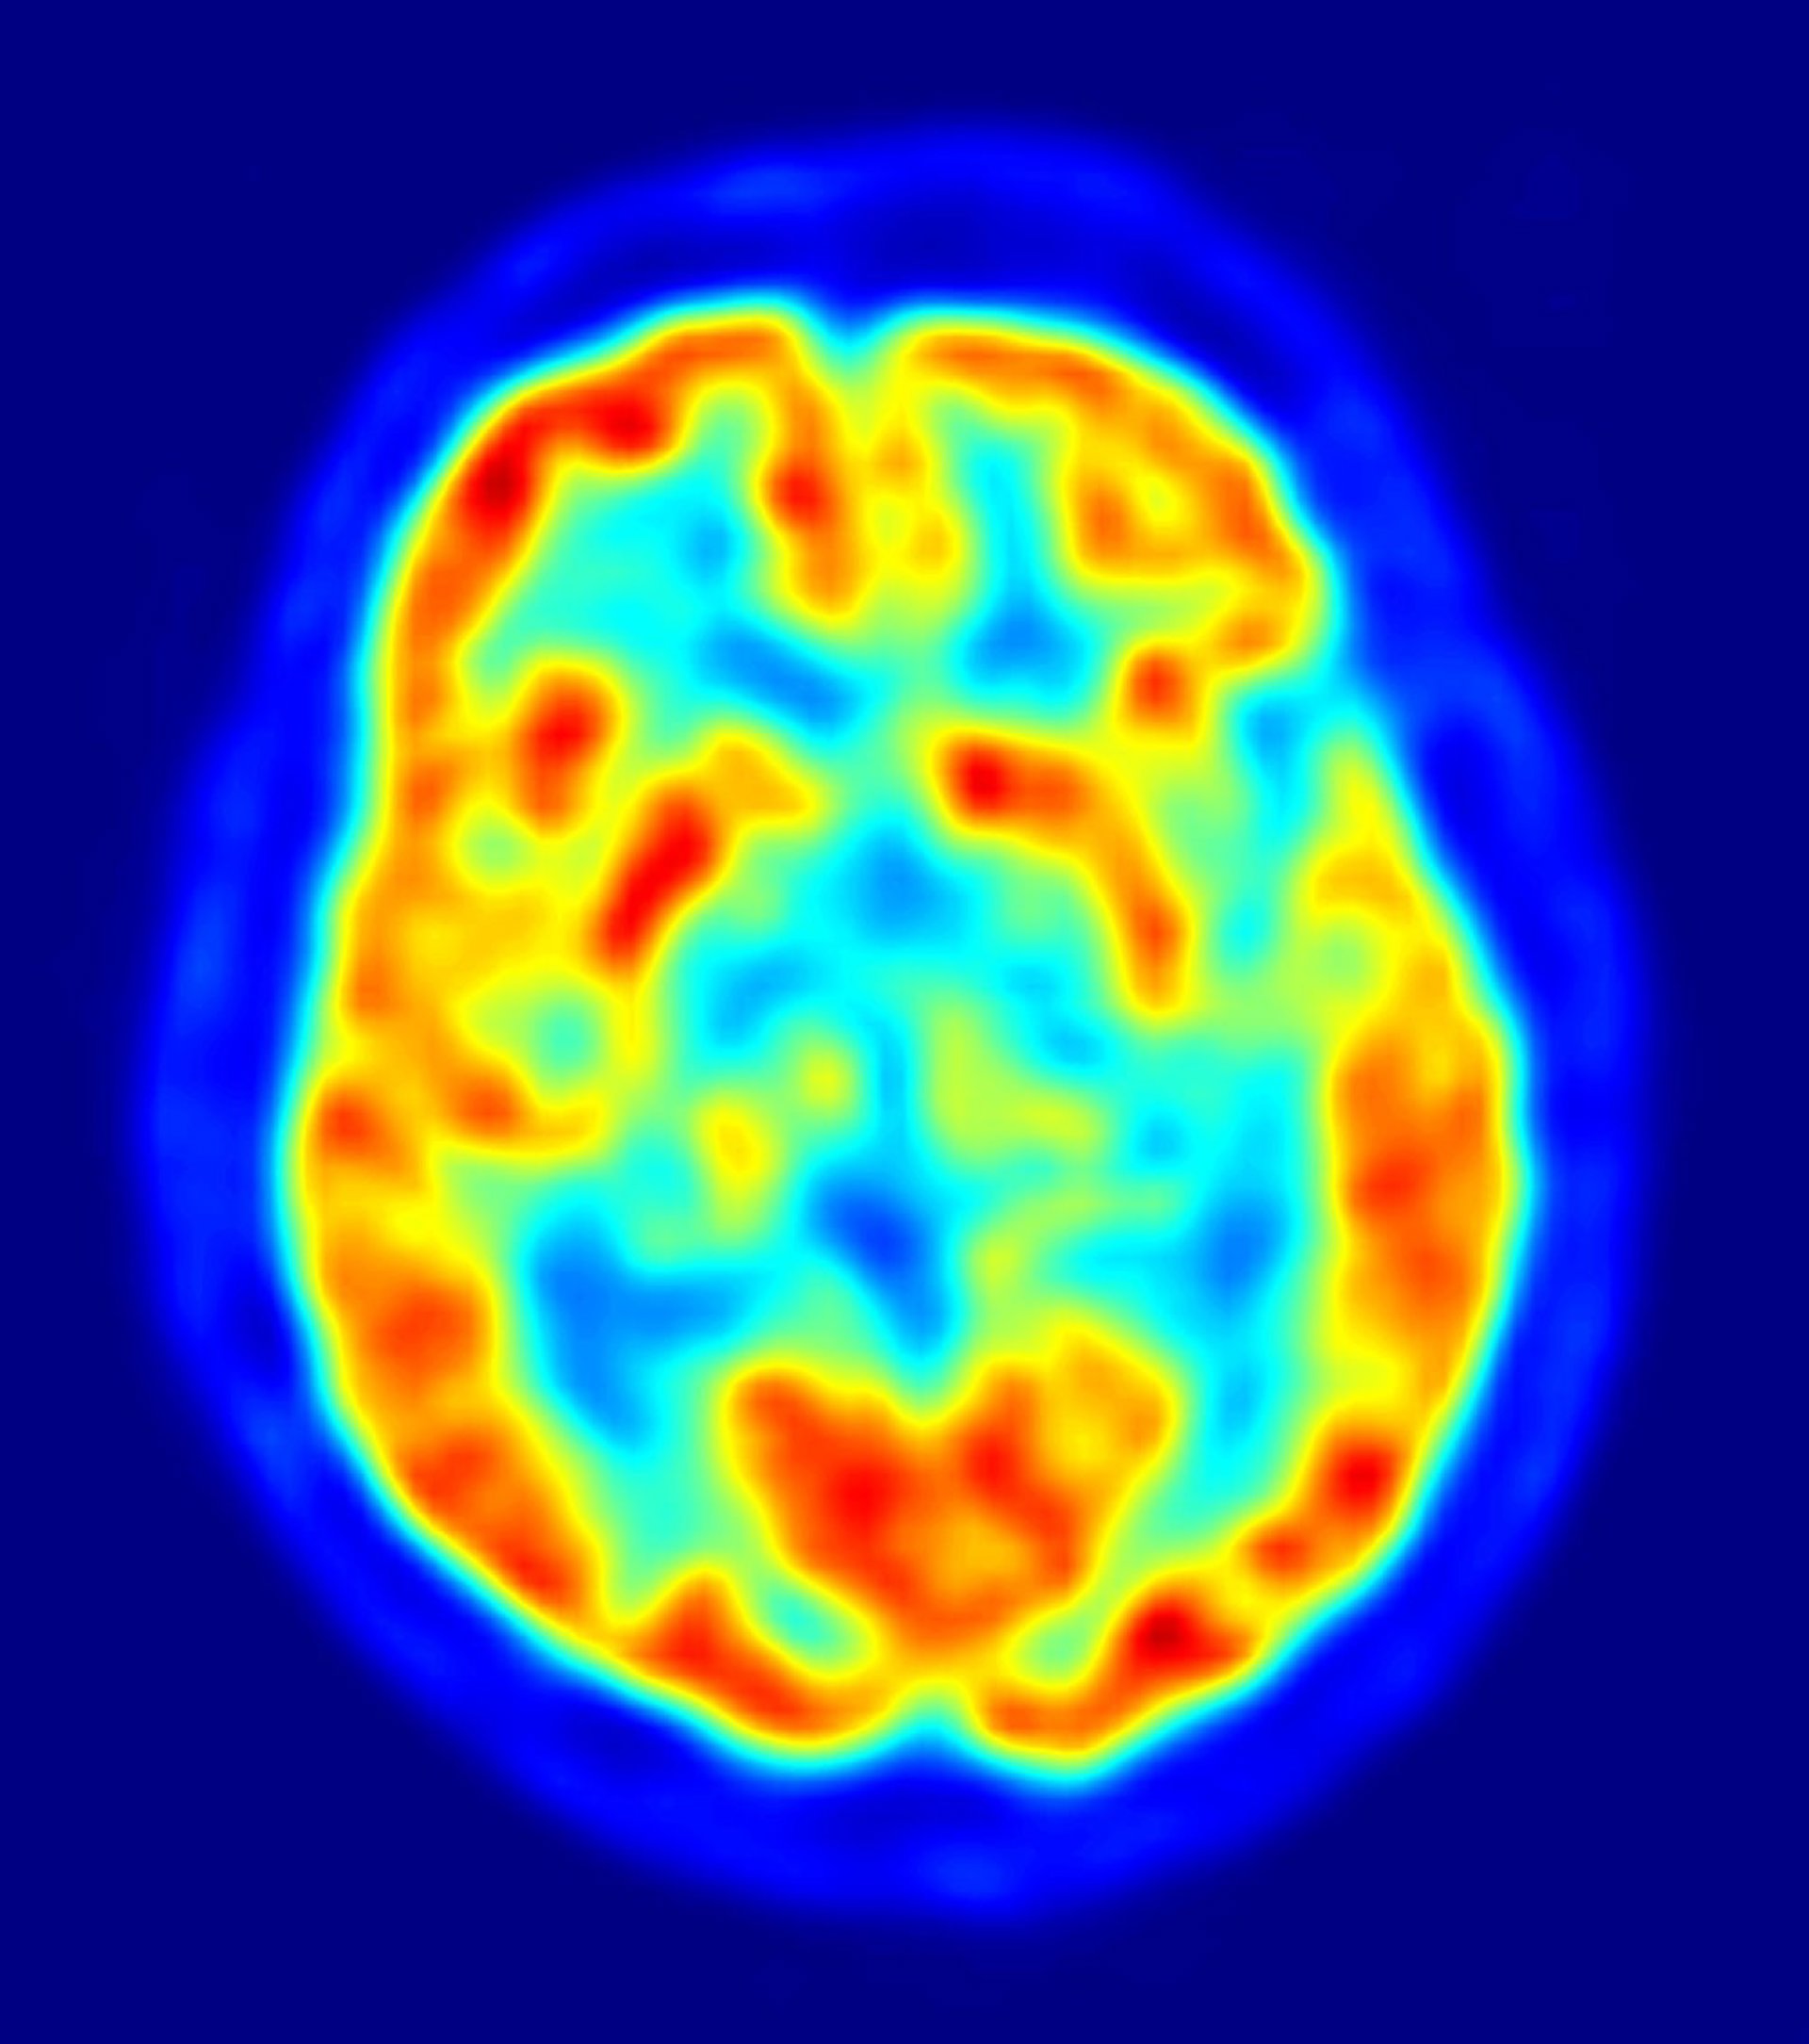

El método de análisis, llamado "clasificación de faro multivariante", divide el cerebro con una malla tridimensional, luego examina cada cubo del cerebro e identifica regiones en las que el patrón de volumen de materia gris podría ser utilizado para discriminar entre los niños con autismo y los niños con un desarrollo típico.

En lugar de comparar los tamaños de las estructuras cerebrales individuales, como han hecho los estudios previos, el nuevo análisis ha generado algo parecido a un mapa topográfico de todo el cerebro. Este tipo de análisis ofrece un enfoque más útil que el anterior. Las estructuras específicas que difieren incluyen la corteza cingulada posterior, la corteza prefrontal medial y el lóbulo temporal medial.

Una vez que Menon y su equipo localizaron el lugar de las diferencias en los cerebros autistas, fueron capaces de utilizar su análisis para decidir qué niños en el estudio tenían autismo. Se utilizó un subconjunto de sus datos en un algoritmo matemático que se aplicó a los datos de los escáneres.

"Podemos distinguir entre niños con un desarrollo normal y niños con autismo con una precisión del 92 por ciento sobre la base del volumen de materia gris en la corteza cingulada posterior", afirma la doctora Lucina Uddin, coautora del estudio y profesora de psiquiatría y ciencias conductuales en la Universidad de Stanford.